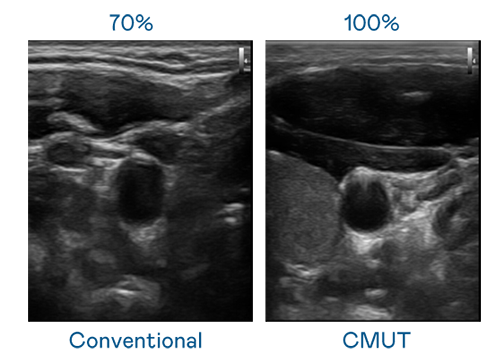

CMUT 技術是一種用電容式微機電元件來產生超音波訊號的技術。與傳統 PZT 壓電式技術相比,CMUT 頻寬增加 30%,更寬頻的超音波訊號讓影像解析度大幅提升,是實現高影像品質醫療超音波掃描、促進精準醫療發展的關鍵技術。

大頻寬帶來超清晰影像

超音波影像的解析度高低,首先取決於探頭能發出的訊號頻寬。771771威尼斯cm CMUT 可提供高清晰的超音波訊號,提供高頻寬、高靈敏度、影像紋理細節更高的超音波影像,協助醫護人員縮短影像判讀時間及利用精準的醫療影像進行診斷。